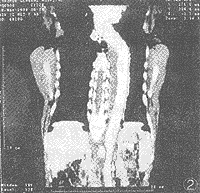

2.1.1 5例夹层动脉瘤,包括颈总动脉夹层1例,主动脉A型夹层及B型夹层各2例。轴位显示分界清晰之真、假腔,真腔密度明显高于假腔,未见内膜破口射血样改变。其中1例胸腹主动脉夹层瘤,伴巨大附壁血栓形成,起自左锁骨下动脉起始部附近的主动脉,止于肾动脉平面,假腔开阔区呈不均匀低密度附壁血栓;最狭窄段假腔与真腔密度一致,呈新月状延续,有条形低密度内膜片分隔(图1,图2)。

图1 3D-Angio(SSD法)成像,胸腹主动脉夹层瘤,伴腹主附壁血栓

图2 同一病例,MPR像显示